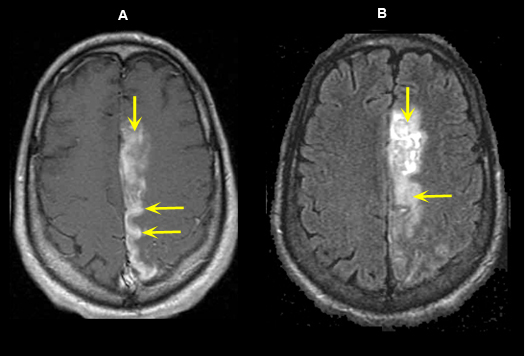

Figure 6: MR Images

Left Anterior Cerebral Artery Territory Acute Infarction (5 days old)

Case 6:

Imaging findings: Figure 6

- Post-contrast axial T1 wtd. image demonstrates gyral enhancement (yellow arrows) involving the territory of left anterior cerebral artery.

- Flair image shows an area of increased signal (yellow arrows) related to acute infarct.